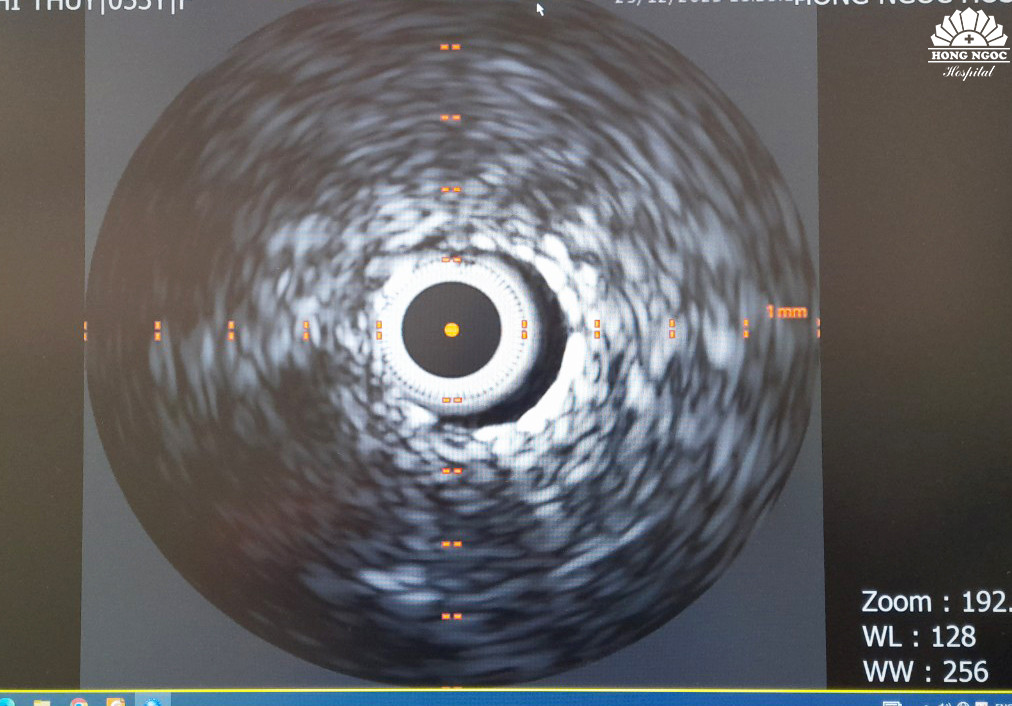

Sau can thiệp, kỹ thuật siêu âm trong lòng mạch (IVUS) tiếp tục được sử dụng để theo dõi kết quả, xem stent đã phủ hết được phần lóc tách hay chưa.

![]() |

| Hình ảnh siêu âm trong lòng mạch IVUS sau can thiệp |

BS.Công cho biết thêm: “Với kỹ thuật siêu âm trong lòng mạch IVUS, chúng tôi có thể đánh giá chính xác mức độ thành công của ca bệnh. Bên cạnh việc hỗ trợ thực hiện đưa stent vào và đặt stent chính xác tại vị trí tổn thương, hình ảnh siêu âm trong lòng mạch cũng giúp quan sát chính xác stent đã phủ kín phần bị lóc tách hay chưa để điều chỉnh phù hợp. Nhờ đó, hạn chế tối đa nguy cơ tái hẹp và tử vong sau can thiệp”.

Kết quả chụp mạch vành và siêu âm trong lòng mạch cho thấy stent đã phủ kín toàn bộ đoạn mạch bị lóc tách, dòng chảy mạch vành khơi thông tốt, ca can thiệp được thực hiện thành công. Sau 3 ngày nằm viện, tình trạng bệnh nhân T.T.Hà ổn định và được xuất viện.